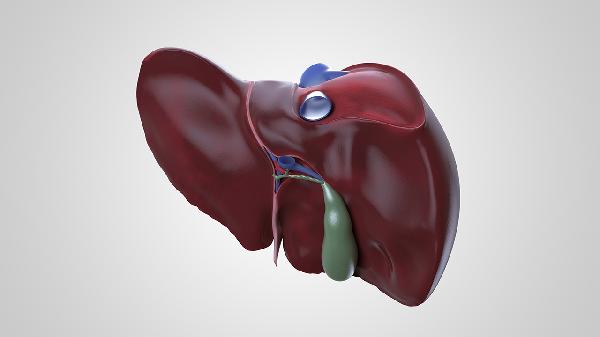

肝脏分泌的胆汁有助于脂肪消化,健康的肝脏能维持稳定的食欲和消化功能。肝病患者常出现厌油、恶心、腹胀等消化道症状,与胆汁分泌异常和门静脉高压有关。

肝脏参与糖原储存和能量代谢,功能良好时能持续为机体供能。肝功能障碍会导致疲劳感加重,这与氨代谢异常、维生素储存不足以及激素失衡相关。

胆汁排泄顺畅有助于形成正常性状的粪便。肝脏异常可能引起大便颜色变浅、脂肪泻或便秘,常见于胆道梗阻、肝硬化等疾病。